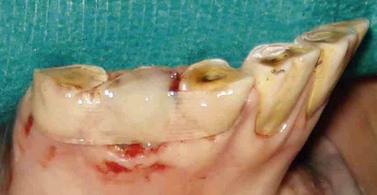

Regardless of the disease etiology, the restoration of a tooth includes two equally important procedures: 1) cavity preparation and 2) selection and application of the restorative materials. Treatment planning for any restoration must include radiographic evaluation of the affected tooth and its surrounding tissues. Radiographic evaluation of the diseased tooth includes evaluation of the pulp, the specific location of the lesion, and the depth and extent of the lesion. Radiographic findings consistent with pulp disease would indicate root canal therapy before tooth restoration. The location of the lesion on each specific tooth determines the forces that will be applied to the restoration. Restorations on the occlusal surface of a tooth must be designed to withstand compressive loading and wear, whereas restorations on the apical aspect of the clinical crown might experience tension or bending stresses. Regardless of the present location of the lesion, all restorations have the potential for eventual occlusal wear due to hypsodontic tooth eruption; therefore, the strength and wear resistance of restorative materials must be considered during material selection. The depth and extent of the lesion must be evaluated to determine the dental tissues involved in the lesion, as well as the proper size and shape of the cavity preparation. Consideration of these factors will determine the required properties of the restorative materials needed to fill the cavity.

Cavity preparation is the surgical operation involving the debridement of decayed or diseased dental tissues in order to shape the tooth to receive and retain the restorative material.2 Regardless of the etiology or location of the lesion, the operator must adhere to the following principles. First, the cavity must be prepared so that all diseased and damaged dental tissues are removed without weakening the tooth’s structure. Inherent in this principle is that as much tooth as possible must be preserved so that the restoration does not compromise the structural integrity of the tooth. Secondly, the cavity is extended to prevent further decay or damage to the restoration. The focus of this extension is the removal of any unsupported or undermined dentin and enamel. To achieve this, the walls of the cavity are formed parallel to the enamel rods, which are usually oriented perpendicular to the tooth surface (Fig. 21.4). Finally, the cavity is configured to facilitate filling, retention, and finishing of the restorative material. This step may include dentinal undercutting for mechanically retained materials and marginal beveling to increase the enamel surface bonding area.3 Advances in modern restorative materials make the necessity of dentinal undercutting debatable.4 Since cementum, not enamel, is the peripheral tissue on the crown of equine teeth and since the bonding of restorative materials to cementum has not been studied, the value of marginal beveling of the cavity preparation is also debatable.